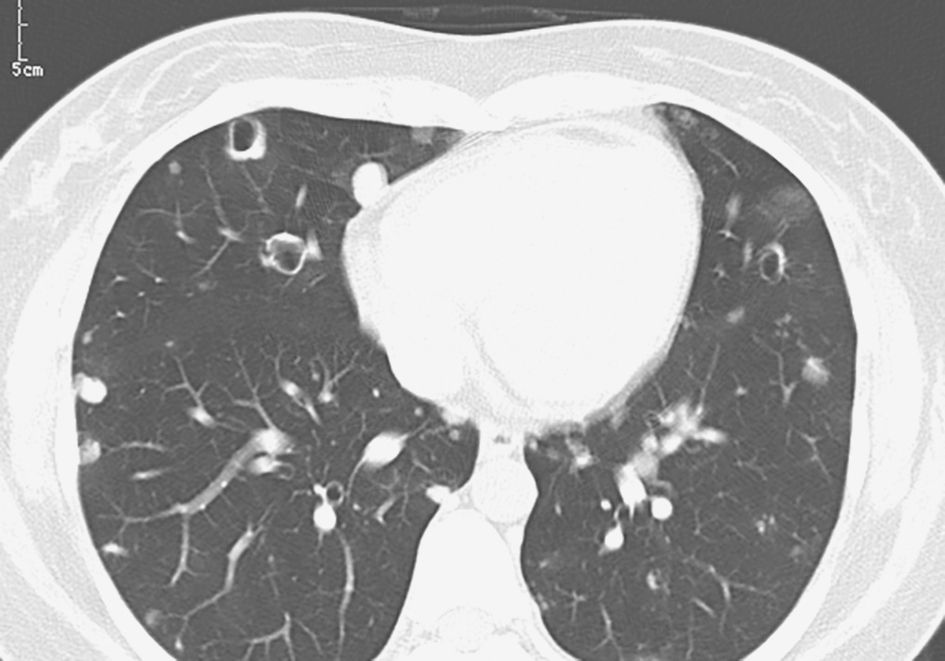

【影像学检查】

经伏立康唑抗真菌治疗7天后,复查胸部CT见右肺中叶病灶有所吸收(图10)。

图10 治疗后复查胸部CT表现

确诊肺毛霉菌病后,用药改为两性霉素B联合氟胞嘧啶。治疗过程中复查肺部CT显示治疗效果较好,但病变吸收较缓慢,需较长疗程。治疗5个月后复查肺部CT发现病灶(左肺上叶及右肺中叶)明显吸收(图13),继续使用两性霉素B联合氟胞嘧啶治疗。

图13 抗真菌治疗5个月后复查胸部CT表现